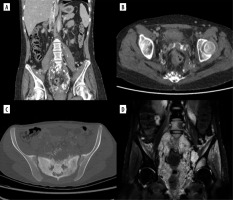

Figure 7

Ultrasound of right breast metastasis in Patient no. 3. A) Axial and sagittal plane. B) Colour Doppler, axial plane

A 14-year-old patient had a lump in her right hand for 7 months, between the first and second metacarpal bones, which was initially assessed as a ganglion. The lesion was finally resected, and histopathological results revealed embryonal partial alveolar RMS. The girl was transferred to our centre for qualification for treatment. In the meantime, she felt a lesion/lump in the right breast. US revealed a nodular lesion 28 × 15 × 28 mm at 12 o’clock with irregular outlines and heterogeneous echostructure (Figure 7), as well as one larger hypoechoic lymph node and several smaller ones in the right axilla.

Figure 8

Exams show the progression of the disease in Patient no. 3 with metastases in the left breast. Ultrasound: A) nodule at 4 o’clock, axial plane; B) nodule at 6:30 o’clock, axial and sagittal plane; C) nodule at 12 o’clock, axial and sagittal plane. D-I) Breast MRI. Status after right mastectomy. Numerous lesions in left breast. D-I) VIBRANT/T1 post-Gd, axial plane

The patient was admitted to our centre for further diagnosis and treatment. On US almost complete involvement of both breasts by heterogeneous, irregularly vascularised nodules was described; in the left breast, the largest ones were located centrally, and had approximately 78 × 73 × 86 mm on the left and 50 × 35 × 42 mm on the right (Figures 9A and B). Additionally, numerous enlarged lymph nodes and a metastasis in the mastoid attachment of the right sternocleidomastoid muscle were found. WB-MRI revealed multiple lesions consistent with metastases throughout the body. On PET-CT, all of them showed increased metabolism of 18F-FDG.

Figure 9

Two ultrasound (US) examinations of breast metastases in Patient no. 4. A, B) Initial examination in our centre. A) The largest nodule in the left breast. B) The largest nodule in the right breast. C, D) The second US after the 4th cycle of chemotherapy. Partial regression of the lesions. C) Nodule in the left breast. D) Nodule in the right breast

The patient was qualified for chemotherapy (VAC), and partial regression of the metastatic and primary lesions was initially achieved (Figures 9C and D).

Figure 10

Magnetic resonance imaging study shows the progression of the disease in Patient no. 4 with new lesions in both breasts and nodules in the pleura. A-D) WATER/T1 post-Gd, axial plane